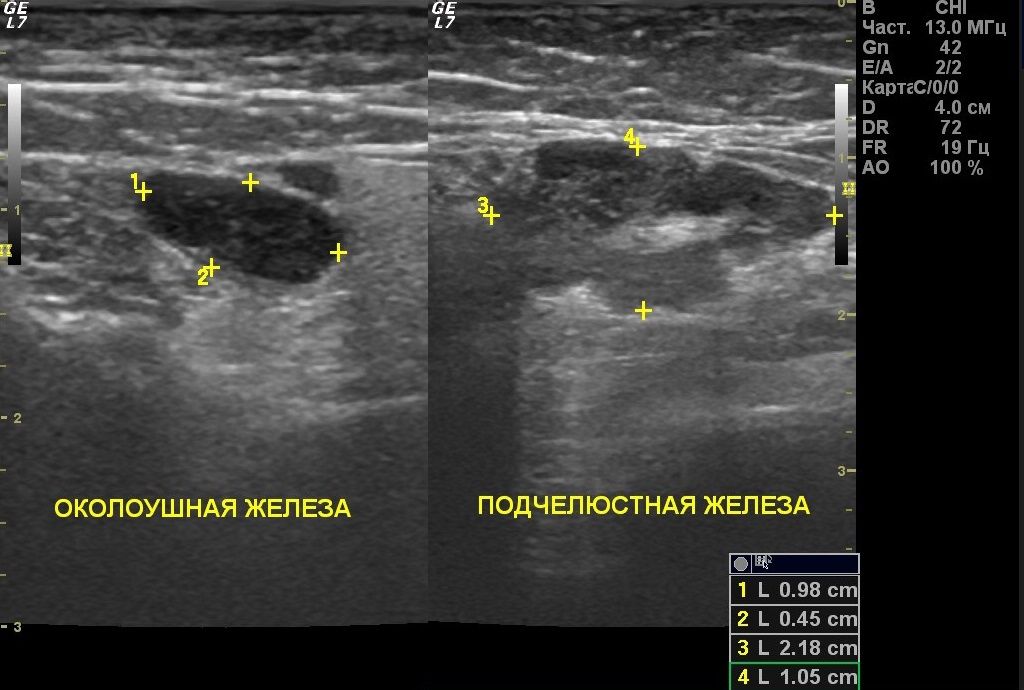

Наиболее эффективным и доступным является УЗИ. Данный метод исследования позволяет выявить в паренхиме железы гиперэхогенные участки, соответствующие воспаленным лимфатическим узлам.